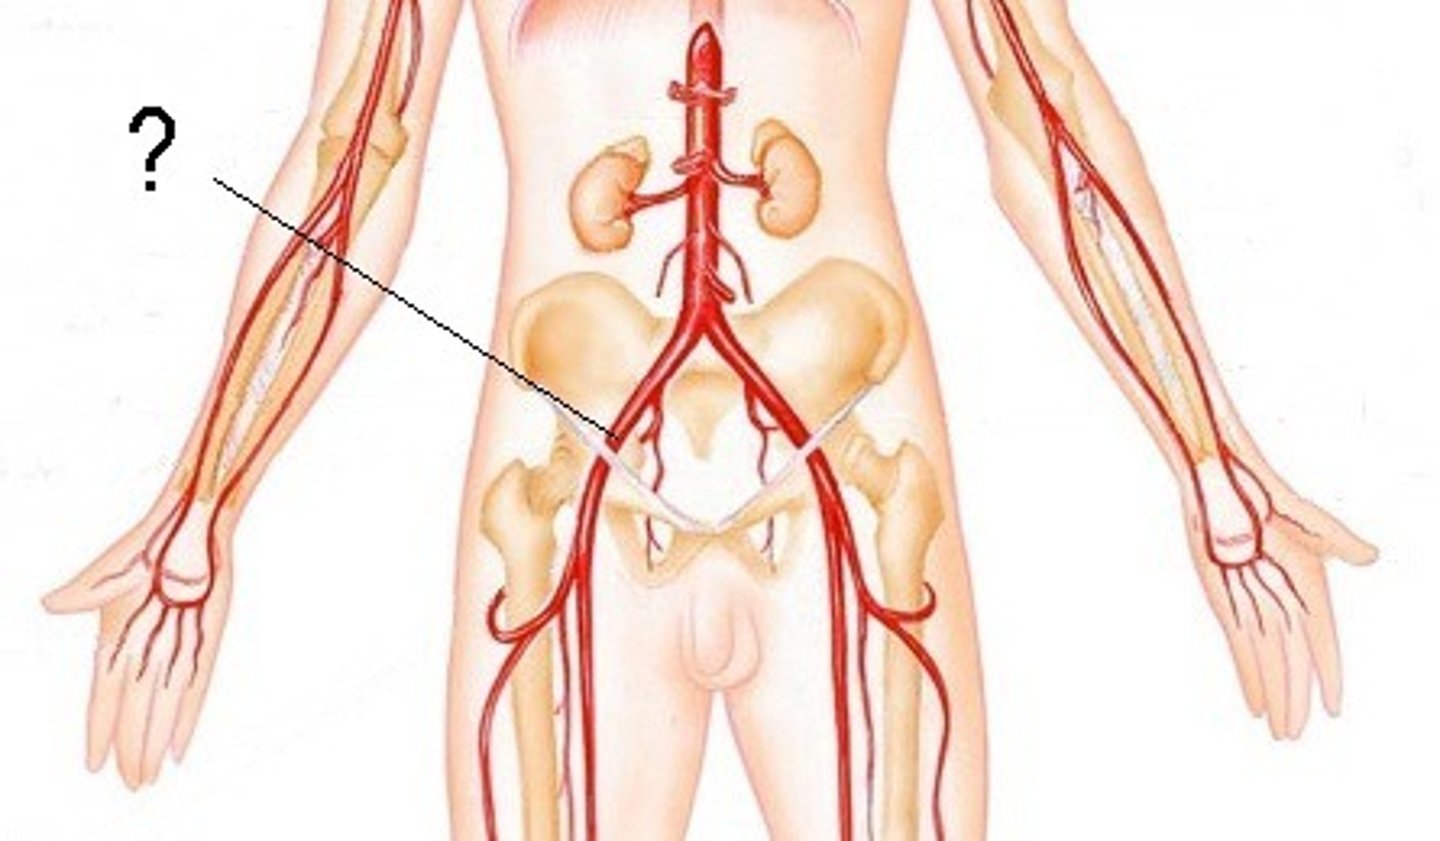

abdominal aorta

renal artery

serves the kidneys

gonadal artery

serves reproductive organs

iliac artery

Serves the pelvic organs, lower abdominal wall, and lower limbs

femoral artery

serves the femur and thigh muscles

popliteal artery

feeds the posterior tibial artery, fibular artery, anterior tibial artery, and dorsalis pedis artery